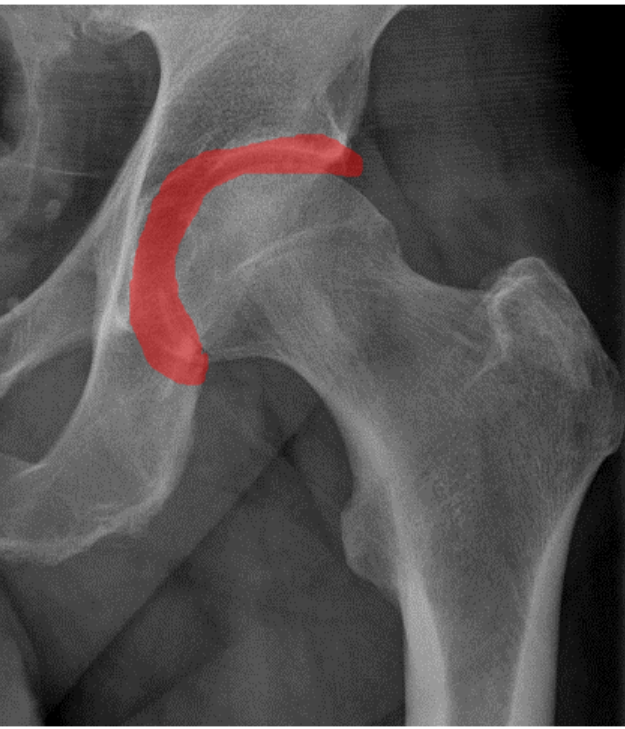

A hip labral tear occurs when the labrum, a ring of cartilage that surrounds the hip joint socket (acetabulum), becomes damaged or torn. The labrum plays a critical role in stabilising the hip joint and ensuring smooth, pain-free movement. Damage to the labrum can cause pain, clicking or locking sensations, and a loss of hip function, which may affect your ability to walk, run, or perform other physical activities.

- X-Rays: X-rays can help detect bone abnormalities, such as femoroacetabular impingement (FAI) or hip dysplasia, which may be contributing to the tear.